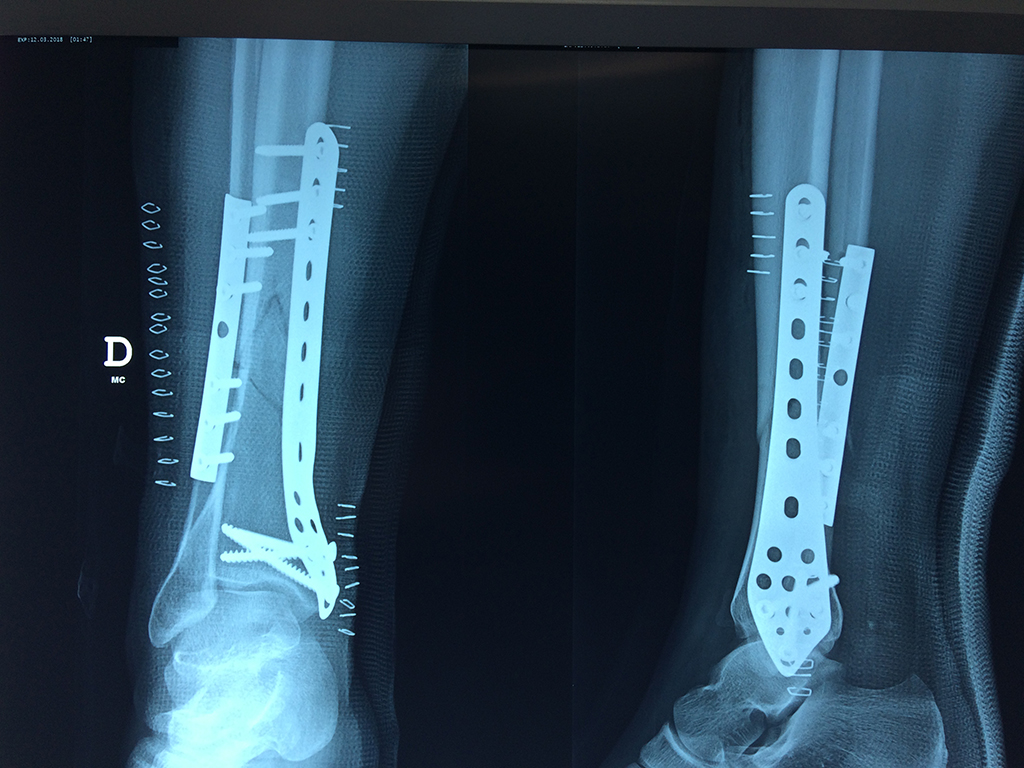

Cirugías de Codo - Perone y Tibia

Aunque cada uno de estos huesos puede fracturarse por separado, normalmente la rotura es una lesión que se produce de forma conjunta

La mayor parte de las roturas implican a la parte proximal del hueso (parte del hueso próximo a la rodilla) o a la parte distal (parte del hueso cerca del tobillo).

Debido a la fina cobertura de piel que recubre la tibia y el peroné, las fracturas generalmente son abiertas, es decir, el hueso roto rasga la piel, atravesándola. Las fracturas de tibia y peroné generalmente se producen por un fuerte impacto o torsión.